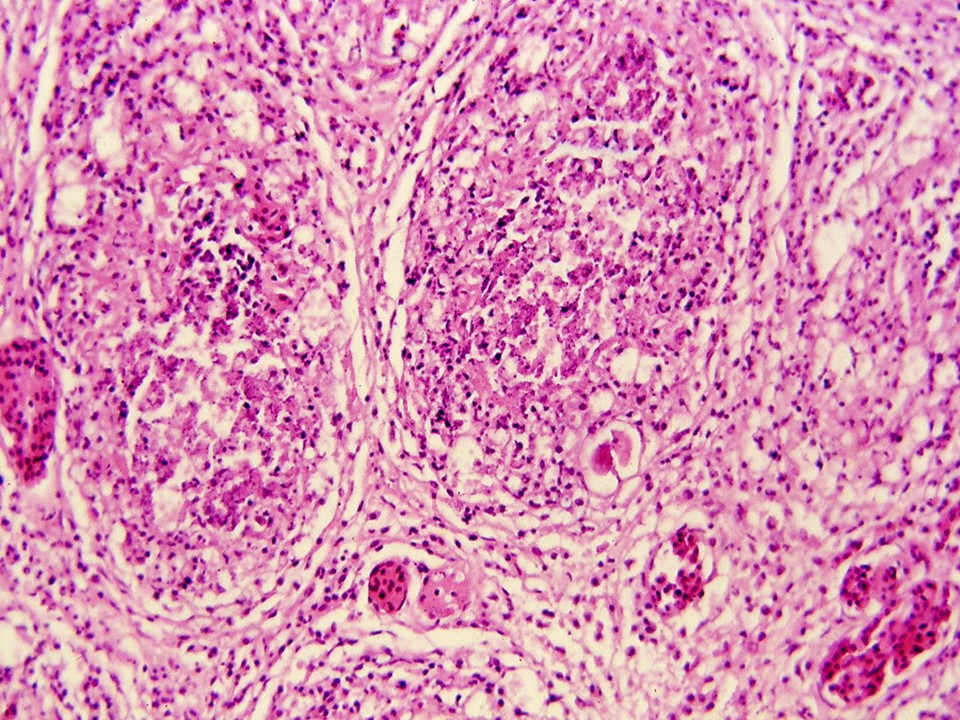

疾病中文名稱:傳染性華氏囊病

疾病英文名稱:Infectious bursal disease;IBD

作者:蔡信雄教授